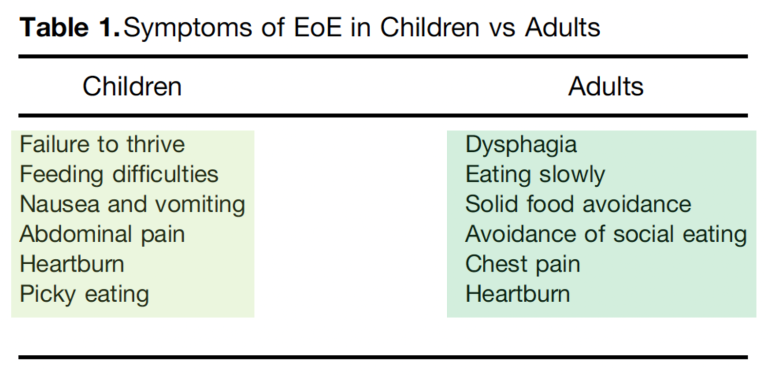

(왼쪽) 내시경소견, (오른쪽) 조직검사소견증상에서 하나씩 살펴보겠습니다.유럽 가이드라인에서는 소아와 성인의 증상을 나누어 설명을 하고 있었습니다. 소아의 경우 역류가 주된 증상으로 구토, 복통, 식사 거부 등의 증상이 있으며 성인의 경우 고형물 섭취가 어렵고 흉통이 일어나는 것으로 알려져 있습니다.

일반적으로 식도와 관련된 증상이 있어 내시경을 받는 환자 중 7% 가까이 호산구 식도염의 빈도가 보고되며 삼키기 곤란, 음식물 관련 증상이 동반되는 환자 중에서는 호산구 식도염의 빈도가 23%-50%까지 올라갈 수 있다고 보고하였습니다. 그러나 중요한 점은 증상과 식도의 조직학적 소견이 반드시 일치하는 것은 아니기 때문에 증상만으로 진단이나 치료경과를 판단하지 않는다는 점을 강조하고 있습니다.역학 호산구 식도염 유병률은 미국 기준 1만명당 4~6명이며, 주로 30~40대 백인 남성으로 밝혀지고 있습니다. 최근 호산구 식도염 유병률이 증가하는 이유는 호산구 발생 자체의 증가와 함께 인식의 증가가 복합적으로 작용하고 있다고 보고하고 있습니다.